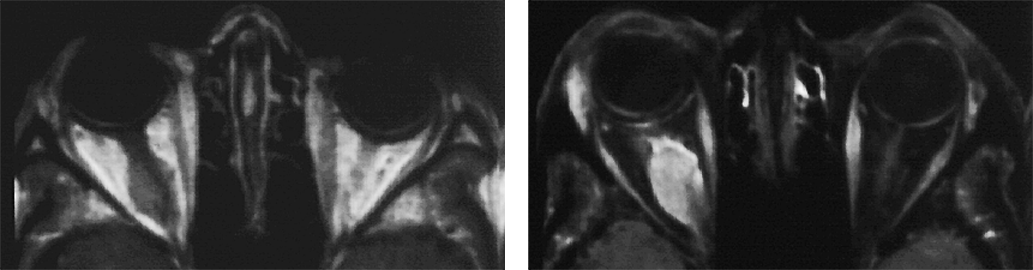

Figura 11-05:

Example of fat suppression — tumor in the right orbit. T1-weighted SE images.

Left: Plain image.

Right: Contrast enhancement of the tumor after gadolinium contrast agent. The tumor has become bright. The fat signal has been eliminated; both orbits now are dark and the enhancing parts of the tu­mor are easily delin­eated.